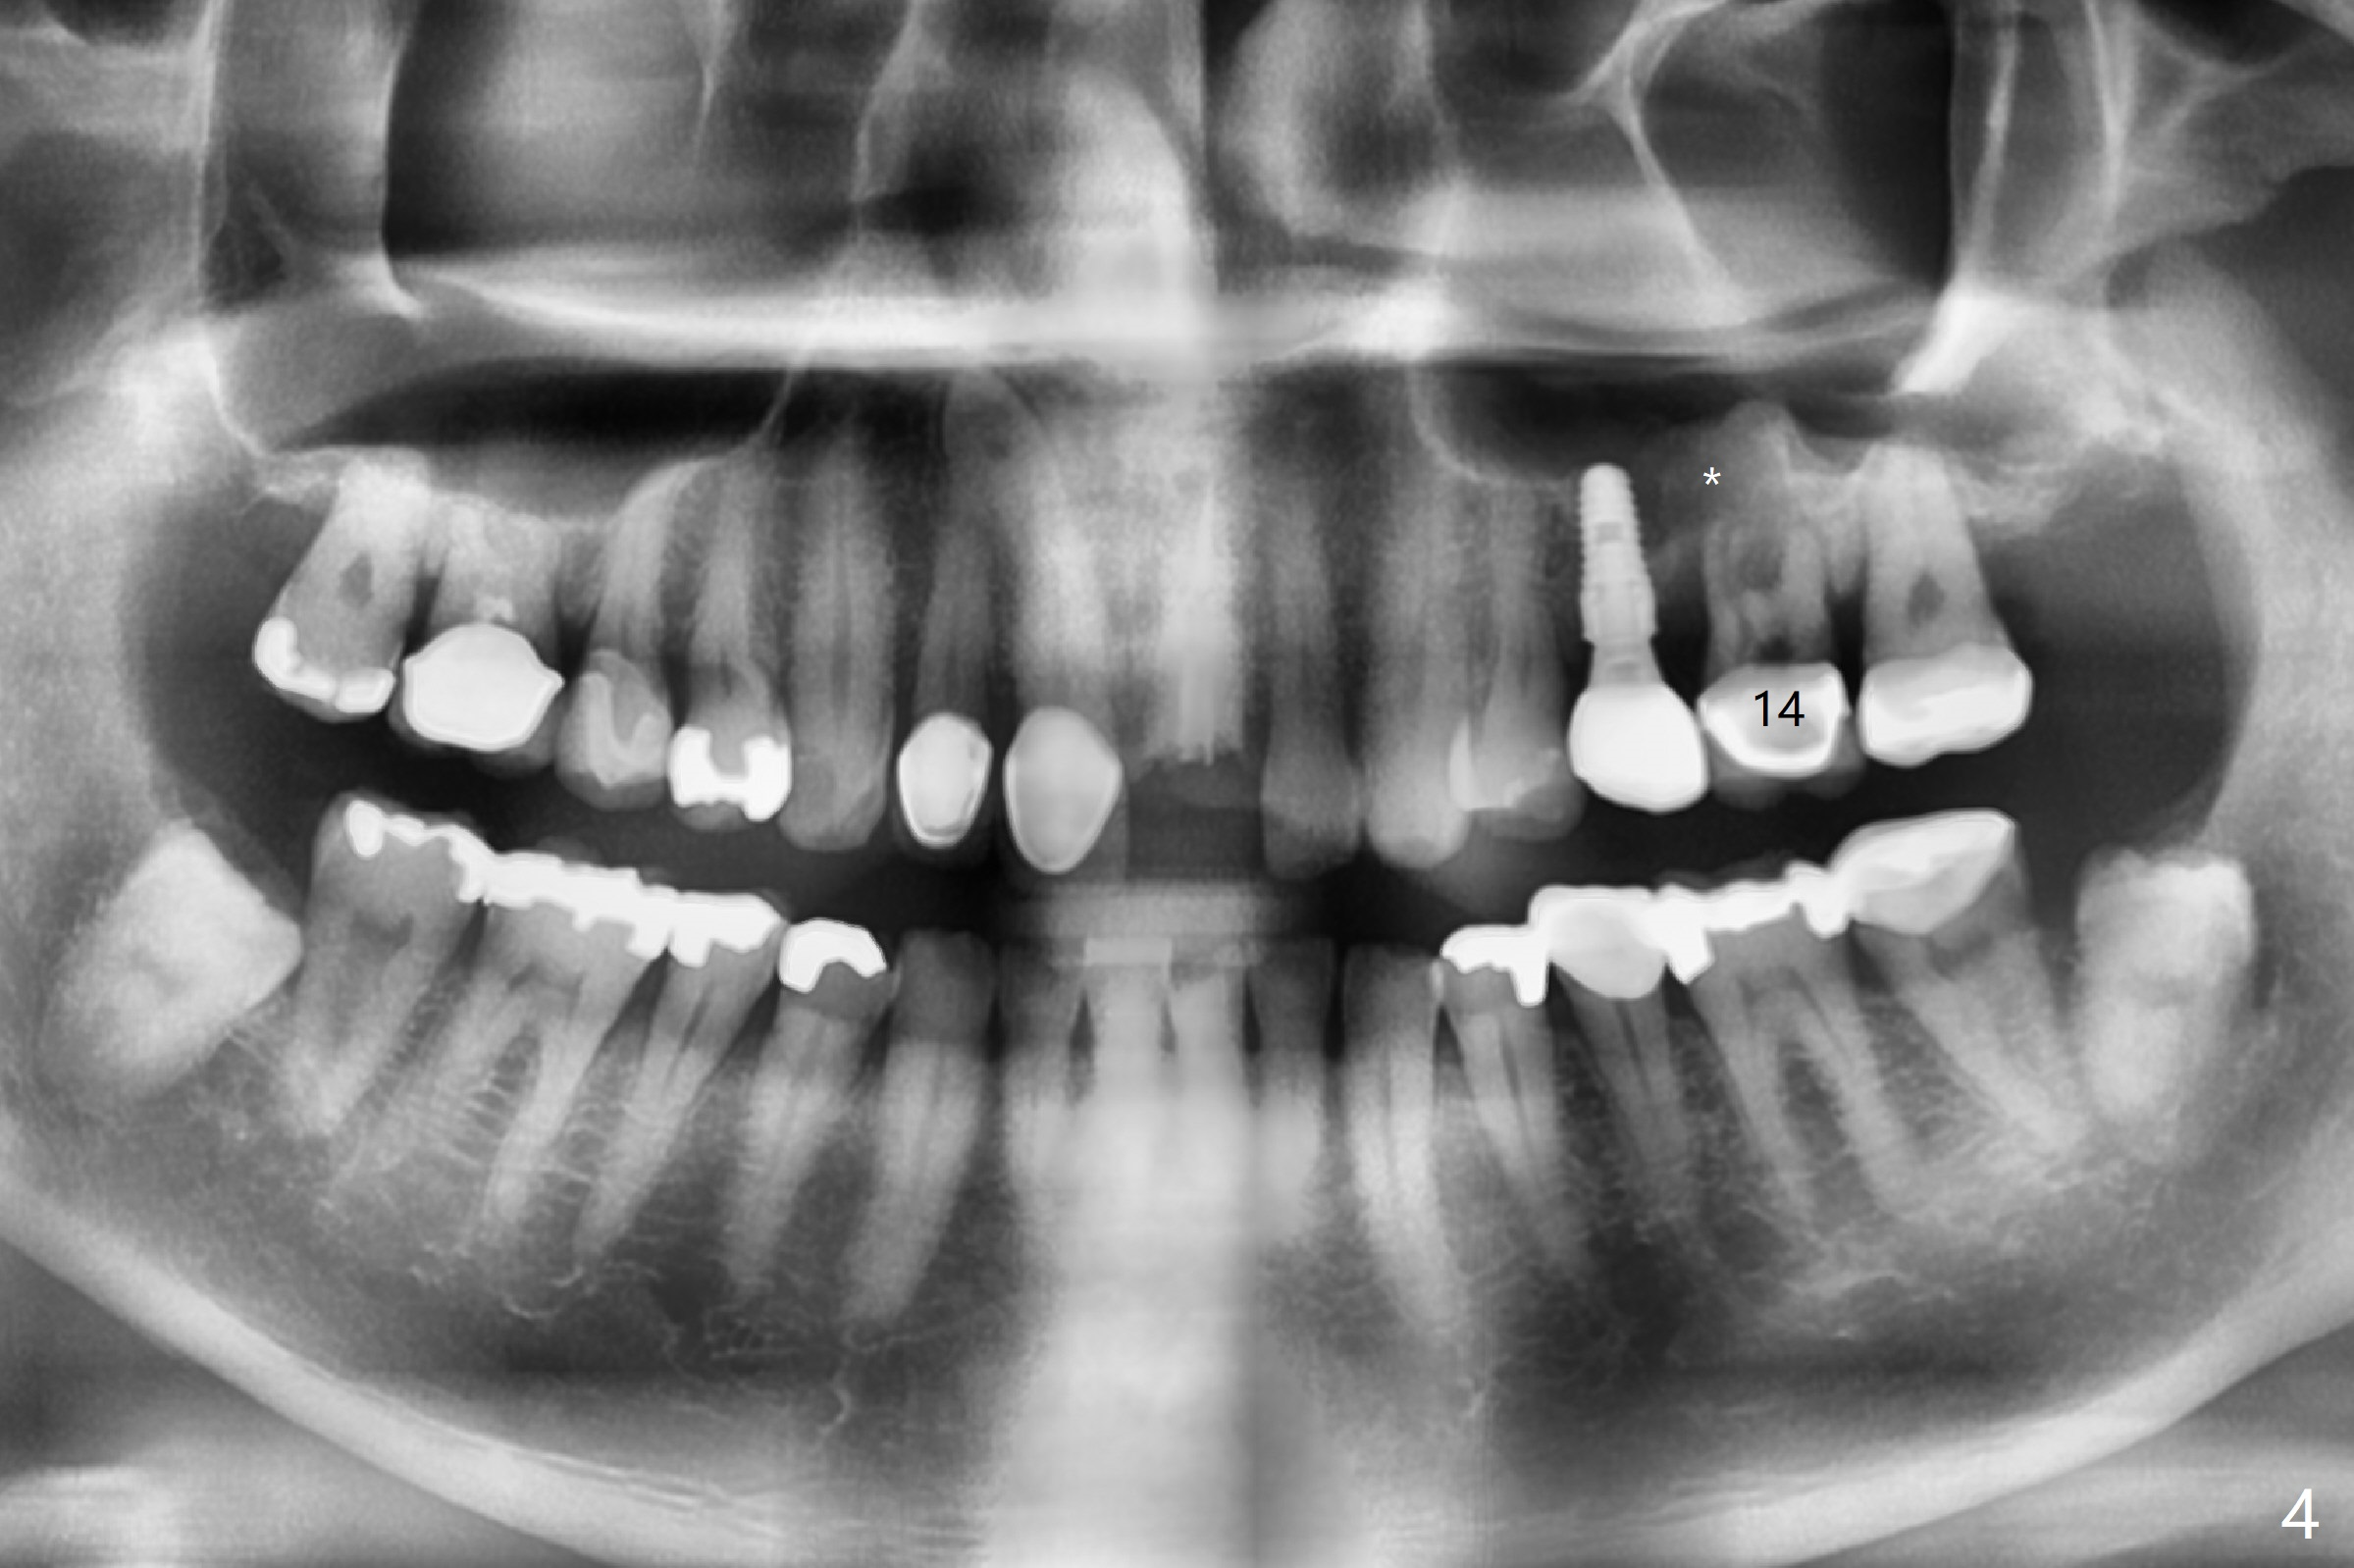

A 58-year-old man fractures the tooth #9 equigingival (Fig.1) and fiber post (Fig.2,3 *). The marginal gingiva is erythematous and edematous (Fig.1 *), suggesting biologic width violation. Redo crown would aggravate the issue. In addition, the mesiobuccal root of the tooth #14 has vertical fracture (Fig.4,5), evidence of heavy mastication. In fact the tooth #13 was also fractured apparently due to heavy occlusion before extraction. It is the best to extract the tooth #9 for implant (Fig.6), or tissue-level (3.5x14 or 17 mm).